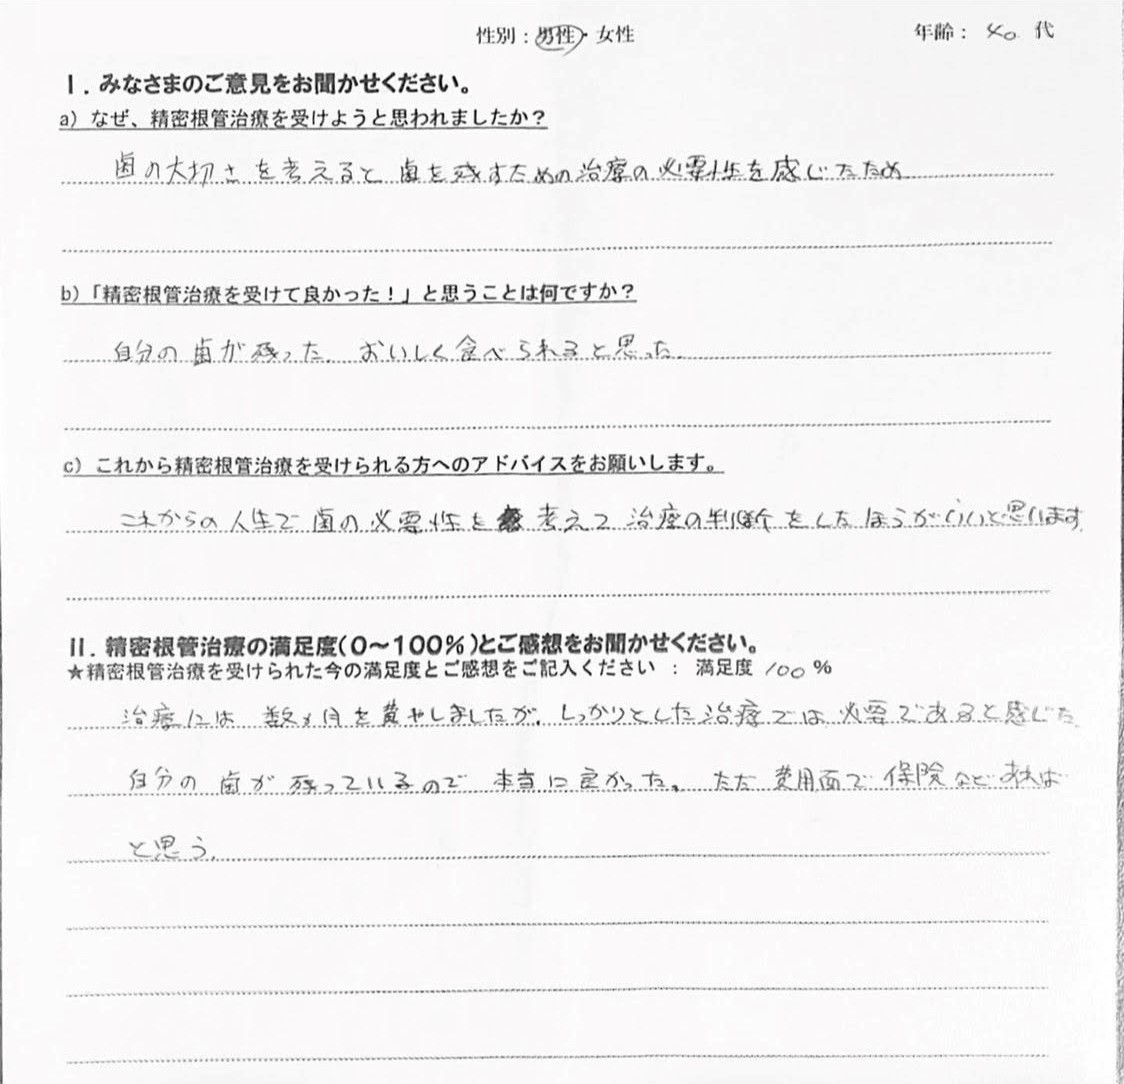

【患者様の声】精密根管治療を受けた40代男性の方です

こんにちは! 南館歯科クリニックの歯科衛生士 山崎です。 歯周専門治療を受けた方の声をご紹介する前に、 2500万円 丸損するかもしれない話をします。 2500万円、これは日本人が生涯にかける医療費の…